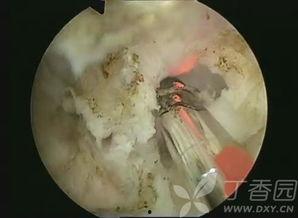

首先,得弄清楚什么是尿道视频。其实,尿道视频是一种医学教育视频,它通过直观的方式展示人体的尿道结构,帮助人们了解这一部位的功能和健康知识。这些视频通常由专业的医疗机构或医学专家制作,旨在提高公众的健康意识。

1. 医学教育:对于医学院的学生和医护人员来说,尿道视频是一种非常实用的教学工具。它可以帮助他们更直观地了解尿道结构,提高诊断和治疗疾病的能力。

1. 解剖结构:这类视频主要展示尿道的解剖结构,包括尿道的位置、长度、开口等。

3. 疾病防治:这类视频针对尿道相关疾病,如尿路感染、尿道结石等,介绍病因、症状、治疗方法等。